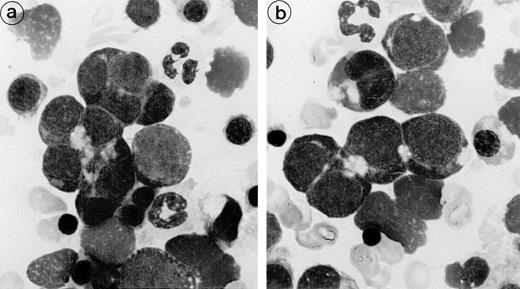

Bone marrow aspirates from the 3 patients showed marked hypercellularity and erythroid hyperplasia (>70% for case nos. 1 and 2). Bone marrow smear from patient 3 showed diffuse lymphocytic infiltration (86%) and numerous erythroid islands (Fig1). The main abnormalities observed in the bone marrow smears of the 3 patients were the presence of numerous erythroid islands, with aggregated erythroblasts and frequent binuclear forms. Most often, adjacent cells shared the appearance of the same maturation stage, but some cells of apparently different maturity were also in close contact. A nonbasophilic clear area was observed at sites of close proximity between adjacent erythroblasts. This feature allowed a distinction to be made between this type of erythroid island and that of sideroblastic anemia. No macrophages were found in contact with these erythroblast clusters.

Bone marrow smear (patient 2): The erythroblasts are numerous and several of them are closely apposed to each other. At the intercellular junction, a clear nonbasophilic zone is evident.

Apart from these abnormalities, the qualitative maturation of the erythroid cell line was normal with a balanced proportion of the different maturation stages, normal nuclear chromatin pattern, and hemoglobinization. Granulocytic and megakaryocytic cell lines displayed a normal morphology.